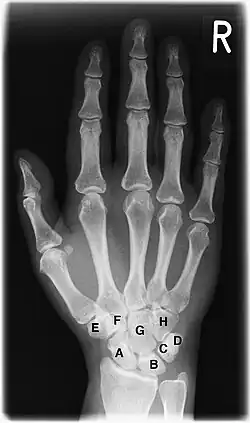

Handgelenk

A–H = Handwurzelknochen

A Kahnbein (Os scaphoideum)

B Mondbein (Os lunatum)

C Dreiecksbein (Os triquetrum)

D Erbsenbein (Os pisiforme)

E Großes Vieleckbein (Os trapezium)

F Kleines Vieleckbein (Os trapezoideum)

G Kopfbein (Os capitatum)

H Hakenbein (Os hamatum)